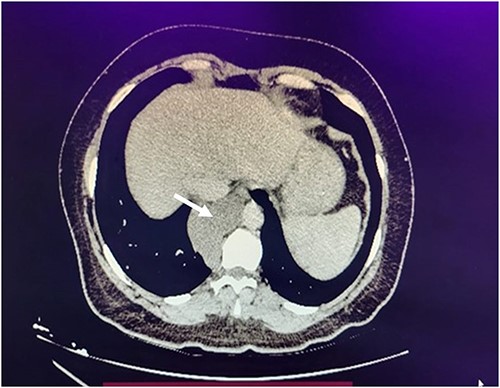

Laboratory results showed abnormal liver function tests, characterized by elevated ALT and AST levels. The liver and bile duct ultrasound revealed hepatic steatosis and hepatomegaly without significant findings. Subsequently, a viral profile was conducted, yielding a positive result for Hepatitis A virus. Due to the persistence of lumbar pain symptoms, an external thoraco-abdominal computed tomography (CT) scan was performed, reporting a nodule in the posterior mediastinum measuring 8.2 cm, which was considered as an infiltrative and/or metastatic lymph node conglomerate (Fig. 1).

Axial chest computed tomography reveals an 8.2-cm nodule in the posterior mediastinum (white arrow).